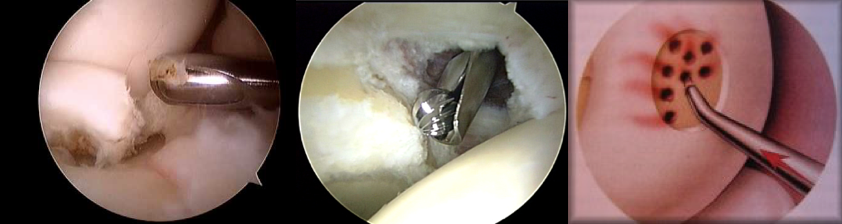

Successful surgical outcomes depend on precision.

Precision Arthroscopic was created to help you achieve exact movements with accurate results.

Arthroscopic instrument technology has now caught up with camera technology, because seeing the problem is only half of the solution.

Our instruments:

-Disposable sterile shavers

-Disposable sterile burrs

-Disposable sterile drills

-All available in straight, curved, and steerable shafts

-2mm and 3mm sizes

-Available for Stryker, Smith&Nephew, and Linvatec shaver systems

-Available for cordless drill chucks